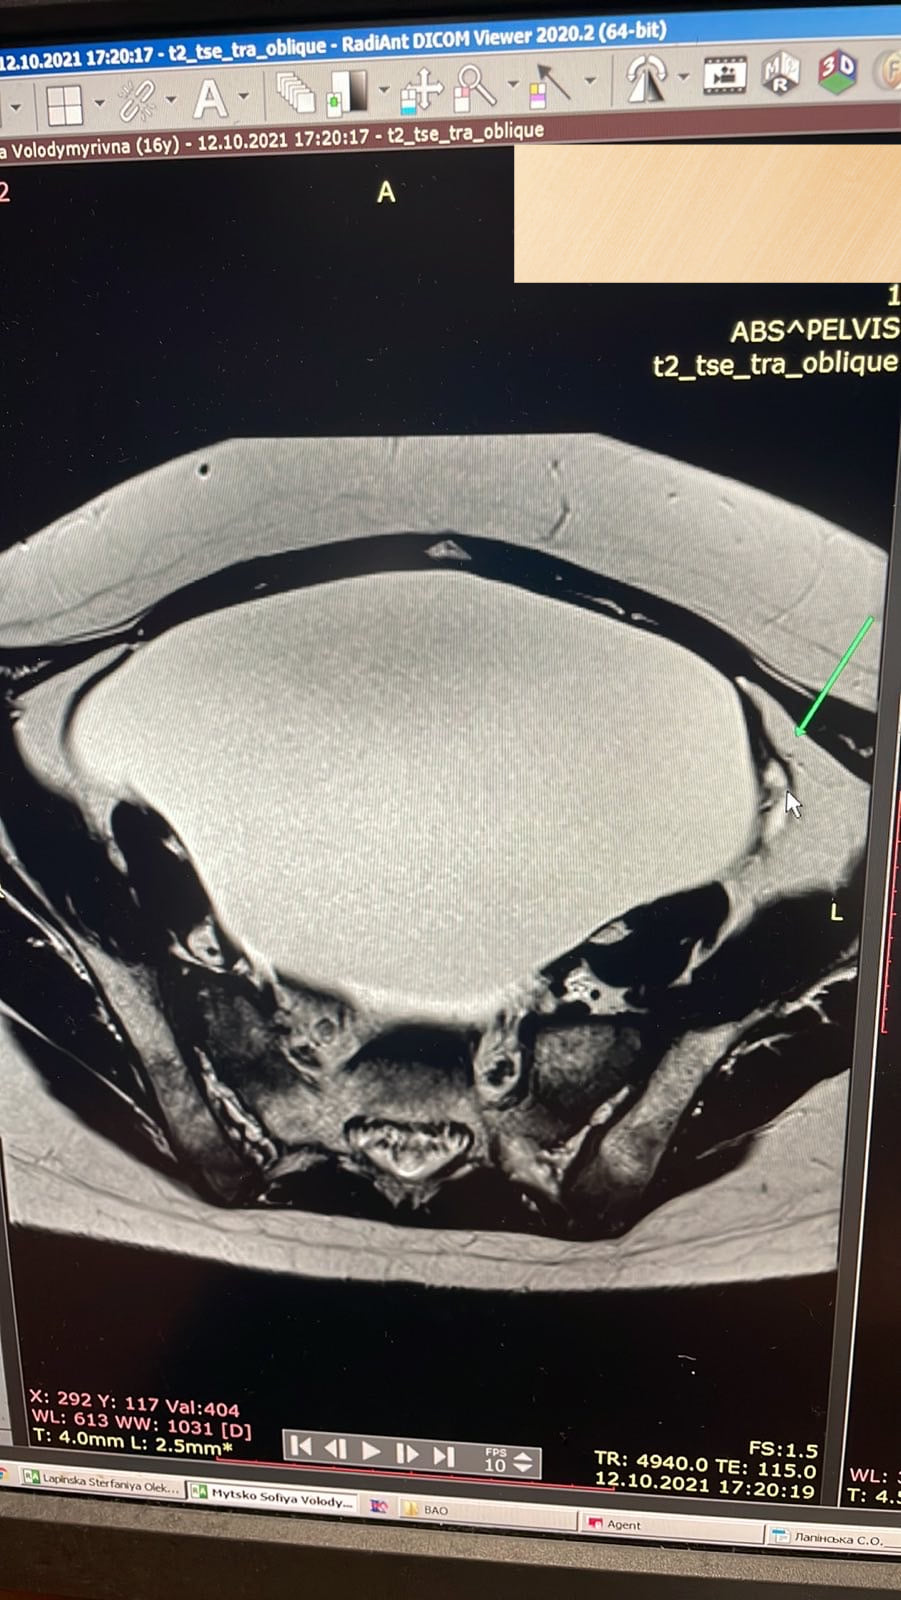

Медики удалили из яичников 3-килограммовую опухоль (facebook.com/OHMATDYTLVIV)

Поэтому львовские медики решили удалять образование с помощью малоинвазивного метода, то есть через маленькие проколы, а не через разрез во весь живот. Отмечается, что врачи удалили около 3 литров жидкости и массивную капсулу опухоли.

“Ситуация была непростой, ведь гигантское образование в яичнике было бомбой и уже даже не замедленного действия. Компрессия окружающих органов и вероятность злокачественной трансформации самой опухоли требовали быстрого реагирования”, говорят врачи.